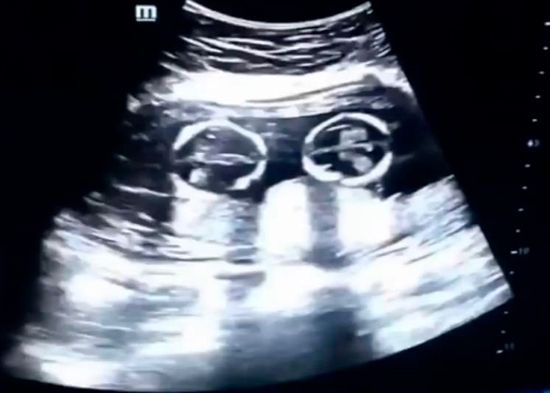

REDACCIÓN INTERNACIONAL.- El video de una ecografía realizada en Yinchuan (Ningxia, China) en la que se ve a dos hermanas gemelas ‘peleándose’ dentro del vientre de su madre, se ha vuelto viral desde que este lunes apareciera en las redes sociales.

Leer más…Una ecografía capta la 'pelea' entre dos gemelas en el vientre de su madre